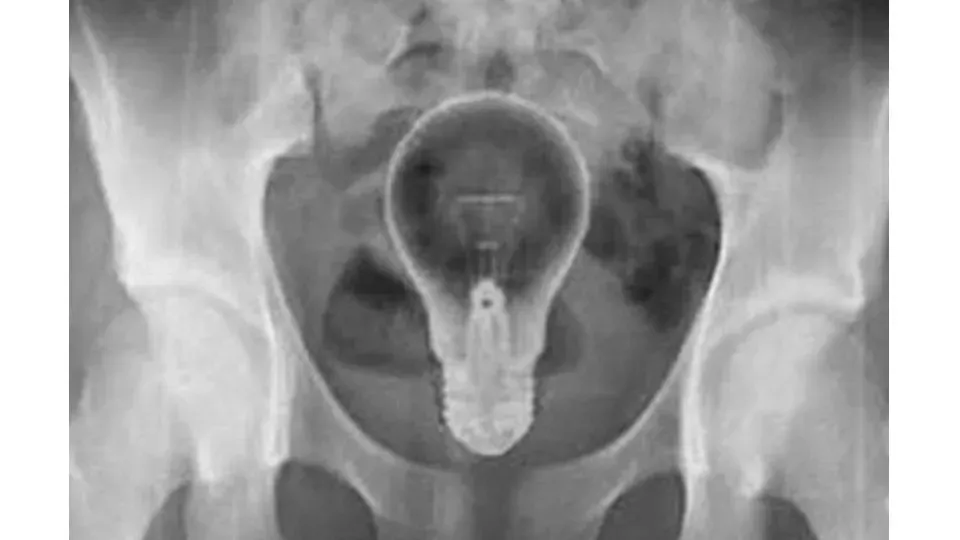

Porto Velho, RO - Na manhã desta quinta-feira (27), um foragido da Justiça teve uma prisão inusitada após pedir socorro na base da Polícia Rodoviária Federal (PRF) na BR-364, entre Candeias e Porto Velho (RO). O homem de 45 anos estava em agonia, com uma lâmpada introduzida no ânus e queixando-se de fortes dores abdominais.